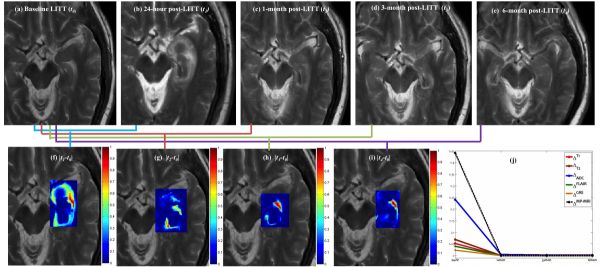

A:LITT技术可能会使病变周围产生水肿。从影像角度看,LITT术后血脑屏障破坏,随后出现新生血管逐渐修复;其他的发现包括外周强化和治疗肿瘤初始边界外的扩散受限。此外,对于一些病灶大的病变,LITT技术可能也不适用,可能出现组织体积增加和水肿效应等。

对于这些副作用如何有效规避?激光热消融后的病灶及周围水肿可能需要额外的药物或手术治疗,以避免神经功能恶化。目前也有一种有计划切除消融组织的方法可以减少水肿的进展,但这需要主治医师拥有丰富的LITT技术经验才能有效避免。